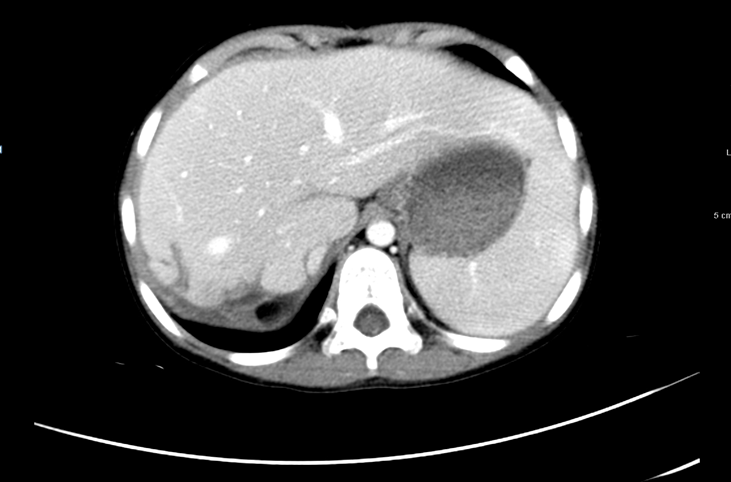

末次化疗后全面复查CT肺部病灶消失。

图6 末次化疗后复查CT